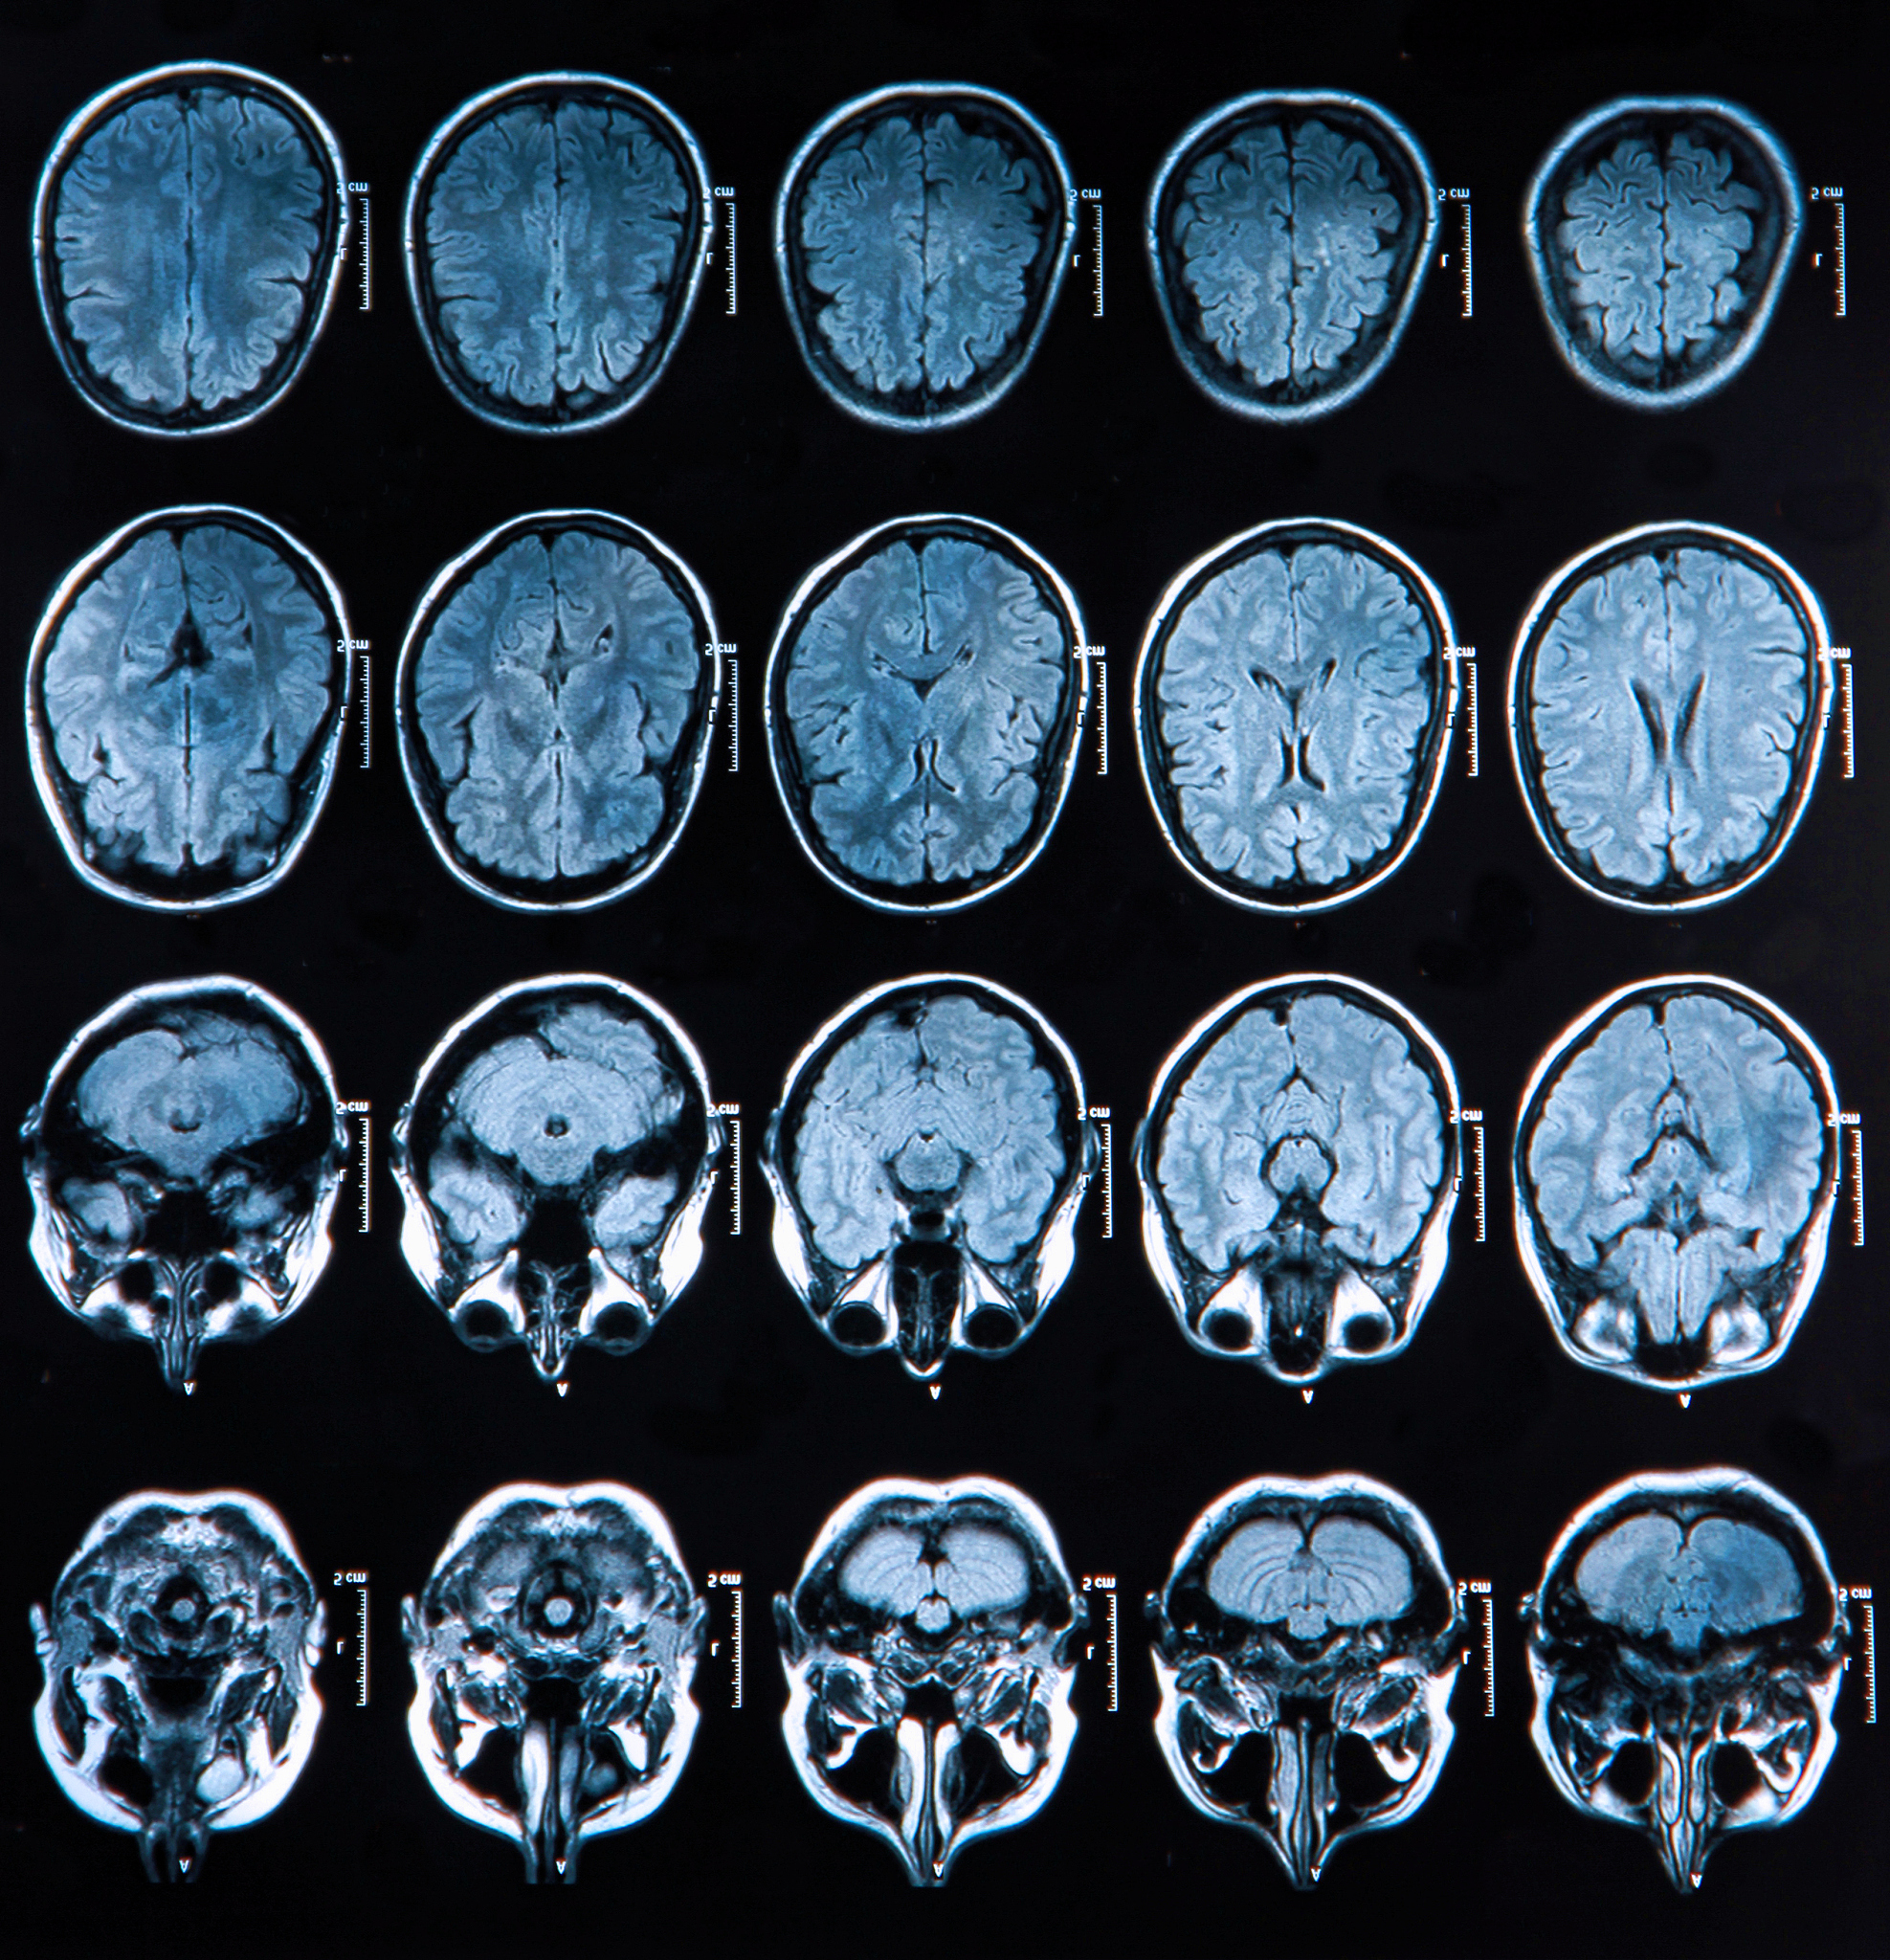

MRI Confirms Right Caudate Nucleus Lacunar Infarction: Evidence of Plaque Rupture and Thrombus Formation

In addition, the patient's MRI showed acute lacunar infarction in the head of the right caudate nucleus, which further confirmed the association of this cerebrovascular event with plaque rupture and thrombus formation.